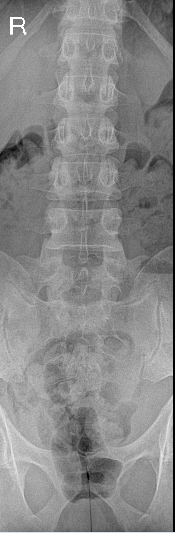

1.png

正位片

腰椎共6节。L6椎体双侧横突肥大,与骶骨形成假关节,符合腰骶移行椎(Castellvi IIb型)的影像学表现。